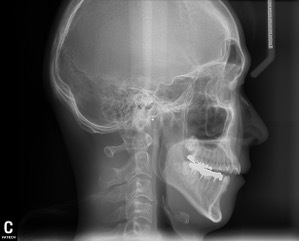

ブラジルの先生も話されていましたが、重要なのは診査・診断です。

術前の診査で、レントゲン写真から導きだされた骨格の角度分析が大変重要になります。